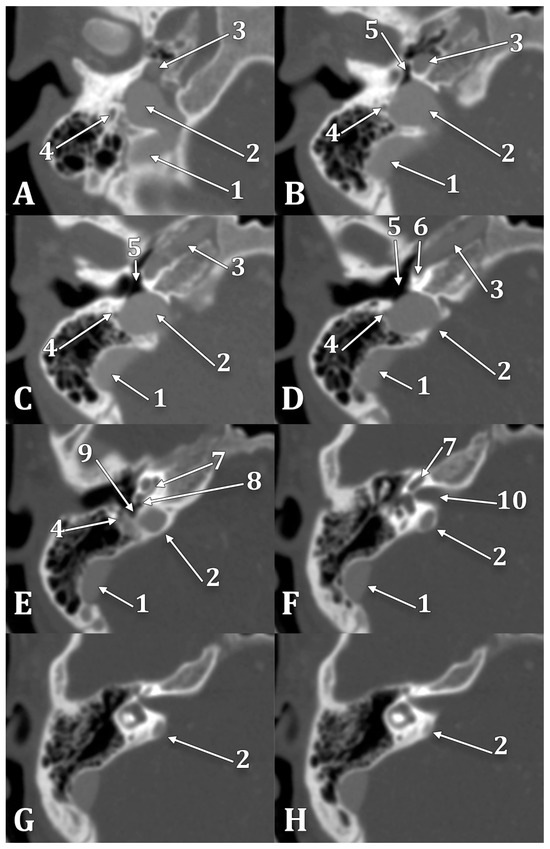

| Type | Subtype | Description |

|---|---|---|

| 1 | no JB | |

| 2 | JB below the PSC | |

| 2A | the JB is not dehiscent into the middle ear | |

| 2B | the JB is dehiscent into the middle ear | |

| 3 | JB between the PSC and IAC | |

| 3A | the JB is not dehiscent into the middle ear | |

| 3B | the JB is dehiscent into the middle ear | |

| 4 | JB above the IAC | |

| 4A | the JB is not dehiscent into the IAC | |

| 4B | the JB is dehiscent into the IAC | |

| 5 | combination of dehiscences |